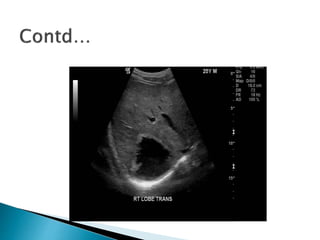

Radiological : This is often helpful in the

diagnosis of hydatid cyst of lungs and liver.

- USG of whole abdomen is useful in locating

the site of hydatid cyst of the abdominal

organ.

- CT-scan is more helpful.